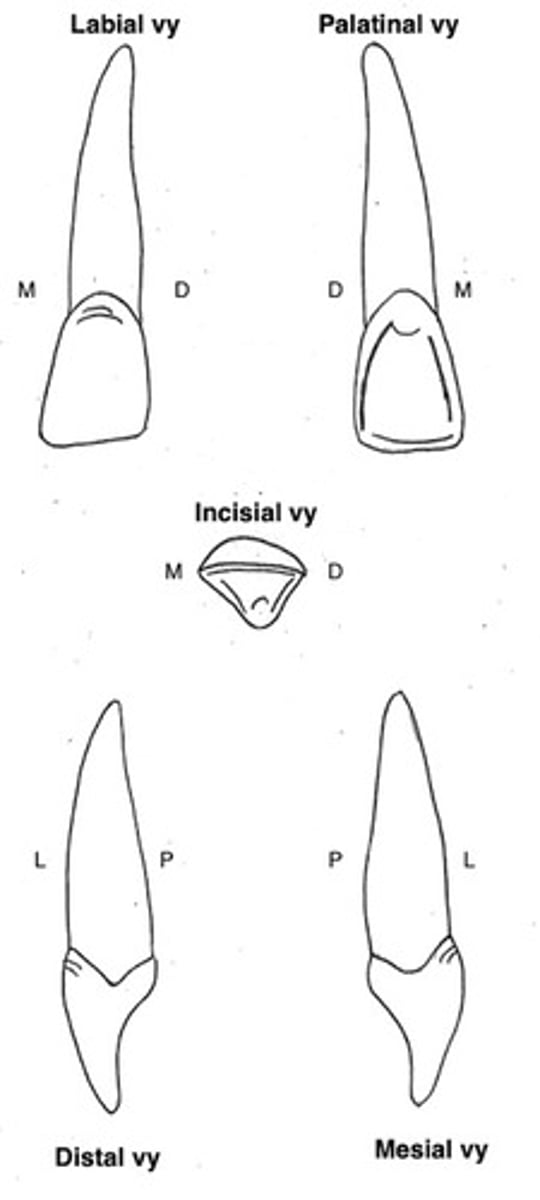

Centralen i överkäken (11 och 21)

Kronans form?

Storlek?

Kronans form

- incisalt skär

- skovelformad

- tydlig limbi och cingulum

- tydligt vinkeltecken

- oftast tydligt böjningstecken

- tydliga mameloner

- palatinal krista

Storlek

- Störst bland incisiverna

- har en kraftig rot